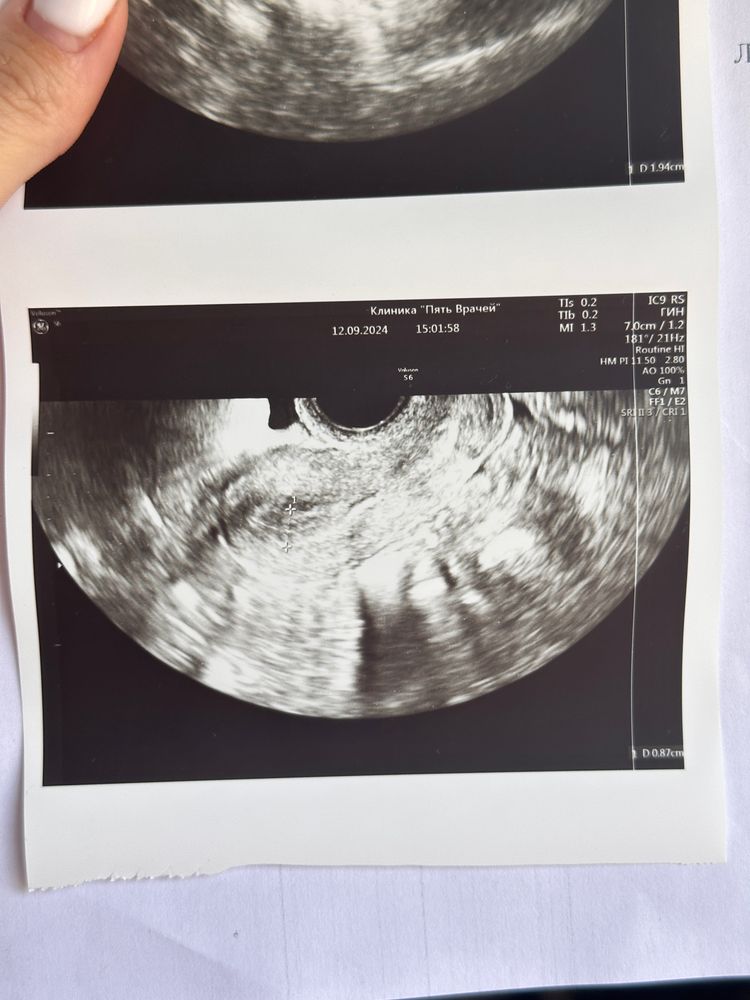

делала узи на 22дц

в узи написано «свободной жидкости в малом тазу физиологическое количество»

есть ещё доменантный фолликул который должен был ориентировочно только сегодня лопнуть

Свободная жидкость означает, что овуляция уже была. Но вы пишите, что доминантный должен ещё только лопнуть

В правом ДФ 17 , в левом ДФ 24

И ещё жидкость в позадиматочном пространстве